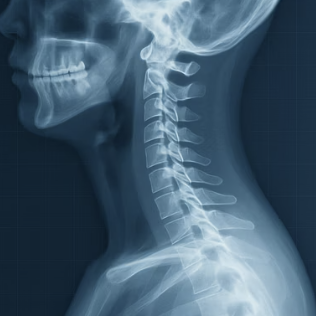

우리 허리는 마치 벽돌을 쌓아 올린 탑과 같습니다. 척추전방전위증은 이 벽돌 중 하나가 아래 벽돌보다 앞으로 미끄러져 나온 상태를 말합니다. 이렇게 뼈가 제 위치를 벗어나면 주변을 지나는 신경 다발이 눌리게 되고, 이것이 허리 통증과 다리 저림의 직접적인 원인이 됩니다.

중요한 점은, 이 문제는 단순히 근육이 뭉친 것이 아니라 뼈의 '구조' 자체가 불안정해진 상태라는 것입니다. 우리 몸은 이 불안정한 구조를 보호하기 위해 본능적으로 허리 주변 근육과 인대를 꽉 긴장시키는데, 아이러니하게도 이 과도한 긴장 상태가 또 다른 통증을 유발하는 악순환을 만들게 됩니다.